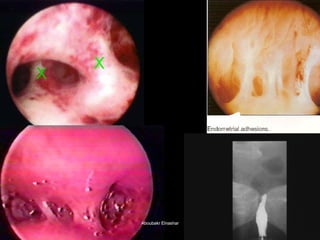

The document discusses the history and development of hysteroscopy. It began in 1869 but did not achieve routine use until improvements to optics, distension media, lighting and instruments in the 1970s-1990s allowed for office procedures without anesthesia. Today, many hysteroscopic procedures have replaced older, more invasive techniques. The document then provides details on rigid and flexible hysteroscopes, lighting sources, distension media, and diagnostic and operative uses of hysteroscopy for conditions like abnormal bleeding, infertility, uterine anomalies and assisted conception. Contraindications are also outlined.